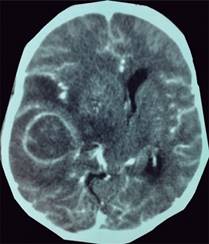

Femenino de 48 años de edad, con antecedente de hipertensión arterial sistémica de un mes de diagnóstico, en tratamiento con losartán 50 mg cada 12 horas. Inició su padecimiento el día 06 de diciembre de 2016, con cefalea continua, holocraneal, intensidad 7/10, que no cedía a la administración de analgésicos, se acompañaba de náusea y vómito; progresó con desviación de la comisura labial, hemiparesia hemicorporal izquierda y somnolencia; por estas razones fue llevada al Servicio de Urgencias a valoración. Se realizó una TAC de cráneo, en la cual se observó a nivel temporal derecho una lesión ovoidea de bordes parcialmente definidos (Figuras 1 y 2), predominio isodenso y con áreas de mayor densidad en su interior (38 a 41 UH), con dimensiones de 42 × 39 mm, la cual reforzó a nivel periférico tras la administración de medio de contraste endovenoso. Alrededor de la lesión se observaba zona irregular, hipodensa, relacionada con edema cerebral; además, desplazamiento de la línea media de 18 mm y compresión del ventrículo lateral derecho. El diagnóstico fue tumoración temporal derecha. Se inició manejo en el Servicio de Urgencias, el cual incluyó uso de esteroides (dexametasona 8 mg IV cada ocho horas), con mejoría de signos y síntomas (reversión de la hemiparesia faciocorporal izquierda y mejoría del estado de conciencia). Ingresó a piso de Neurocirugía; posteriormente, se realizó exéresis completa de la tumoración, con reporte de probable glioblastoma. Ingresó a la Unidad de Cuidados Intensivos (UCI), donde se brindó manejo neurocrítico. Durante su estancia se mantuvo con dexametasona.